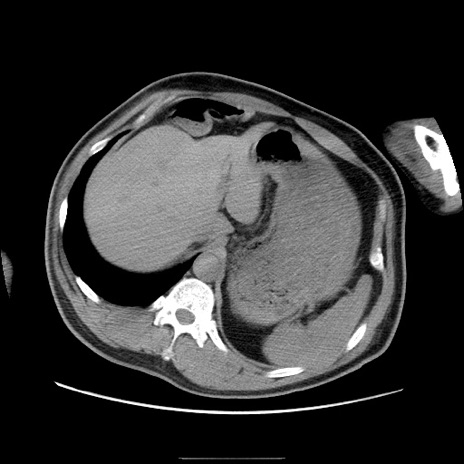

症例22(横断像)

【症例】50歳代男性

【主訴】腹痛

【現病歴】AVMからの被殻出血のため回復期リハ病棟入院中。 本日午後3時頃急に下腹部痛が出現した。

【既往歴】AVM、被殻出血、虫垂炎、高血圧

【身体所見】意識晴明、左半身不全麻痺、会話の理解は良好、36.5°C、腹部:膨隆、全体に板状硬、下腹部正中に圧痛点あり、反跳痛-、筋性防御不明、右下腹部にope scar

【データ】WBC 9400、CRP 0.06